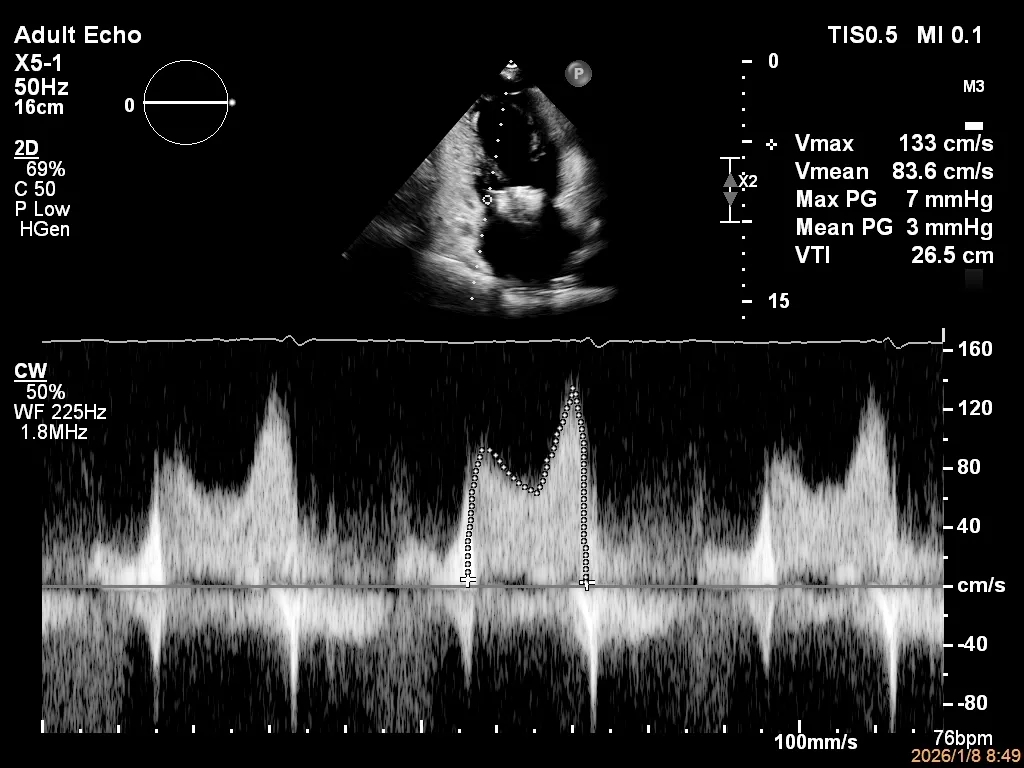

第二枚XTR植入后瓣口平均压差3mmHg

第3枚XTR夹合器植入后,跨瓣平均压差为3mmHg

肺静脉收缩期逆流消失,频谱形态基本恢复正常

术后2D TTE:

术后TTE可见二尖瓣微量-轻度反流,三尖瓣反流明显改善降至中度